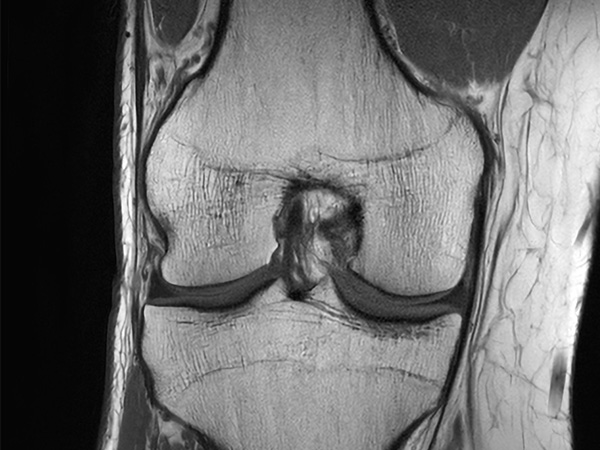

Fast Knee imaging with SmartSpeed Precise